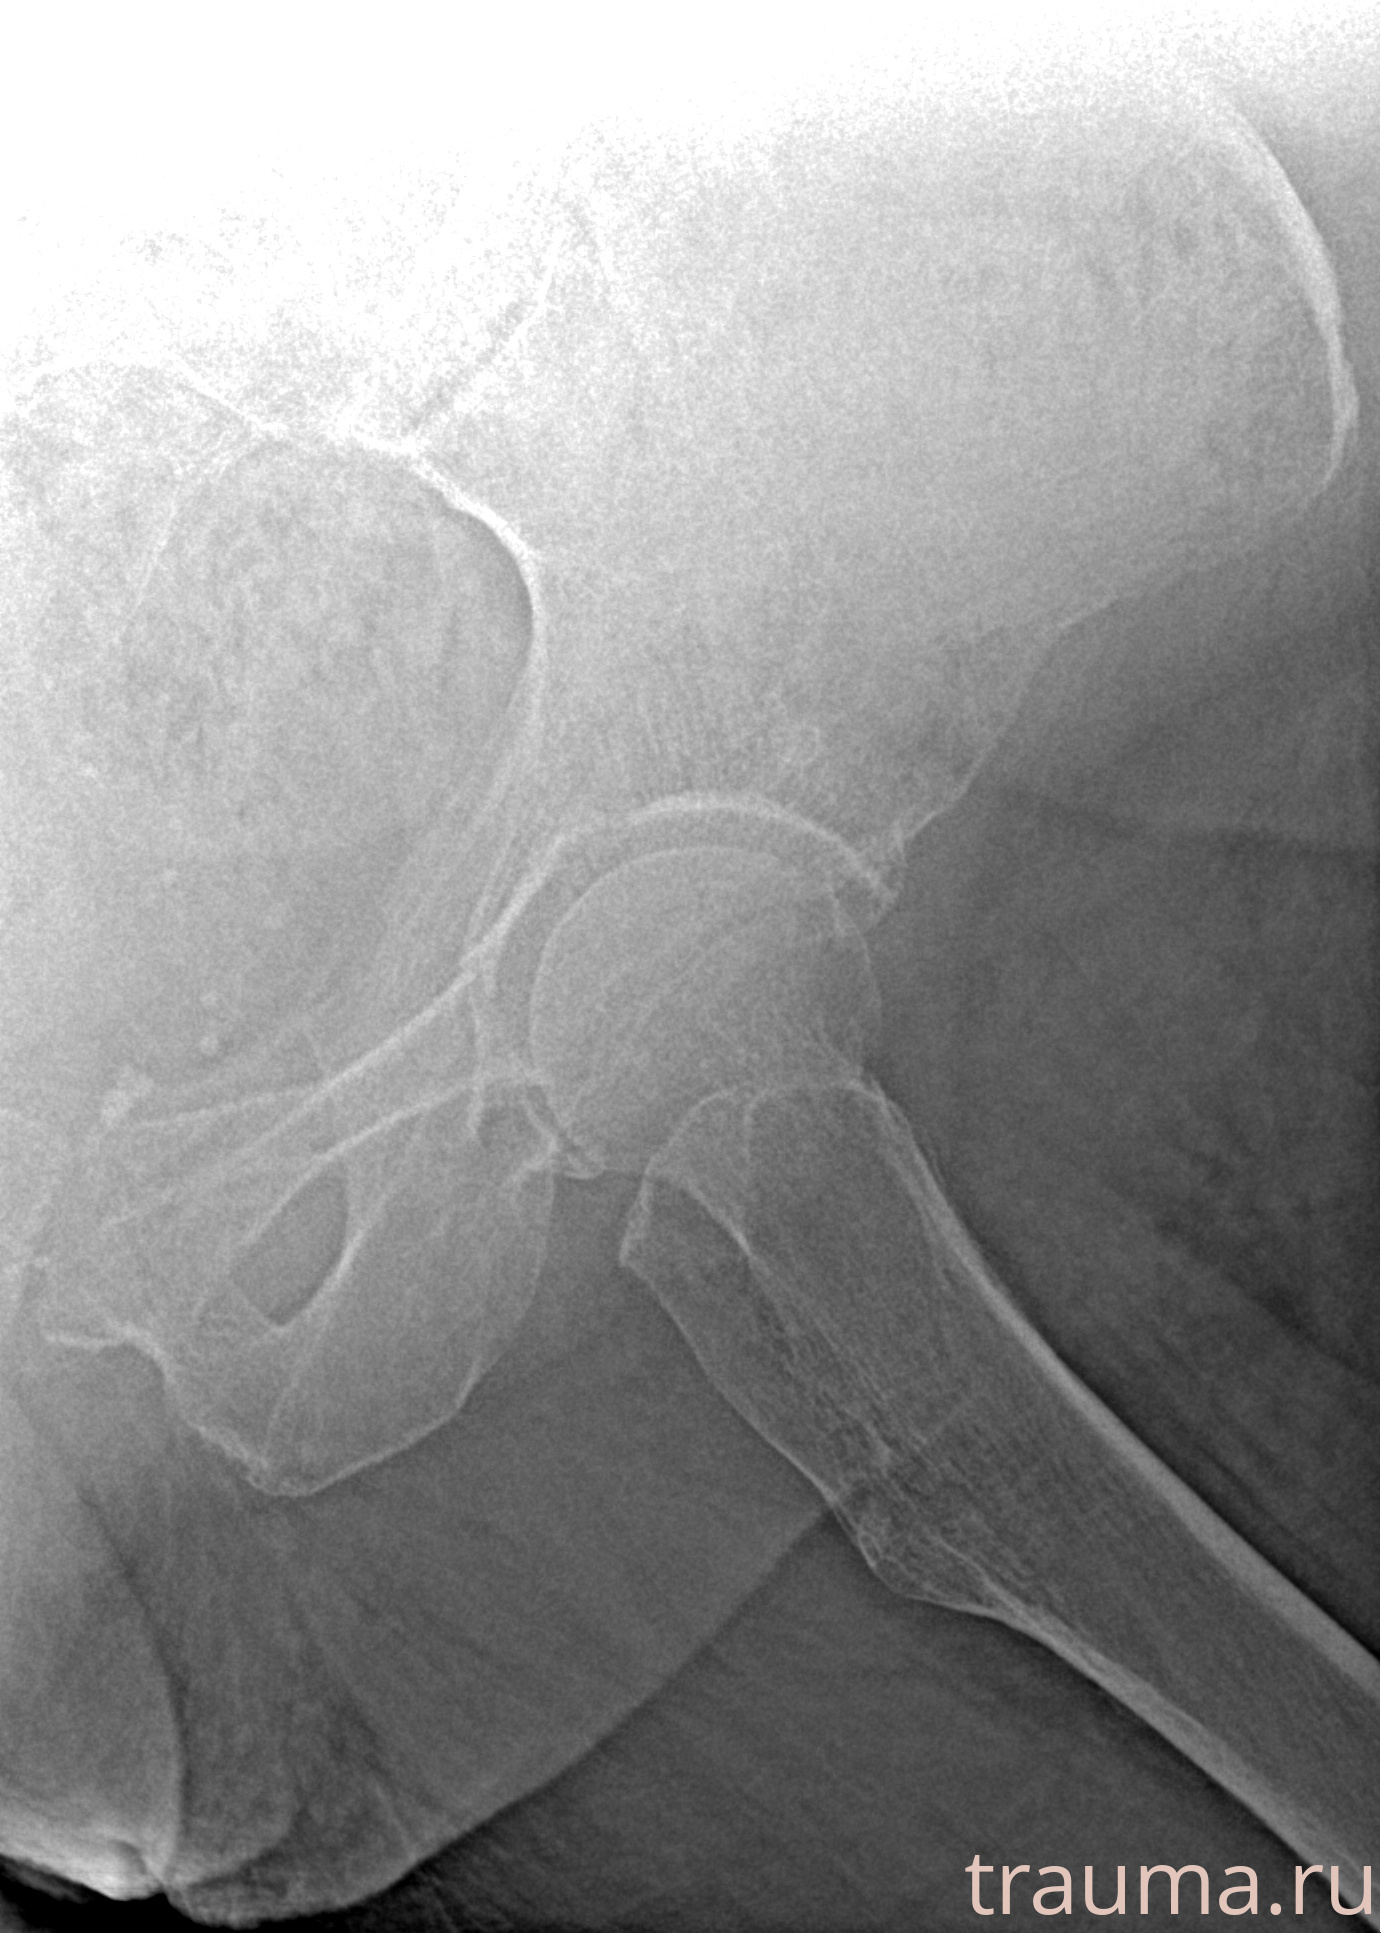

Рентген на дому: по вашему адресу приезжает врач-рентгенолог, травматолог-ортопед с мобильным рентгеновским аппаратом, проводит диагностику травмы или заболевания, делает необходимые рентгенограммы, дает рекомендации по дальнейшему лечению. Получить качественные снимки в домашних условиях возможно благодаря уникальной методике, разработанной МосРентген Центром для института  Склифосовского